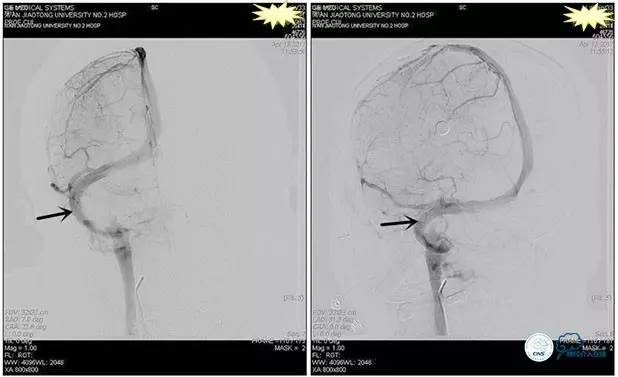

术后造影

术毕远近端压力差为:0

术中右侧ICA造影

右侧ICA斜位及窦内造影

右侧ICA斜位

窦内造影及路图

术中测压:

远端:520mmH2O,

近端:190mmH2O。

术后右侧ICA造影

术后远、近端压力差为:0

术后右侧ICA斜位